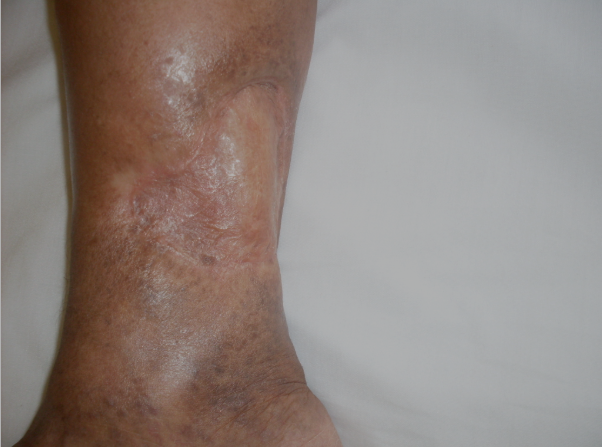

ÚLCERA VARICOSA - caso 09

Evolução Clínica

Giro de resultados antes e depois deste tratamento específico.